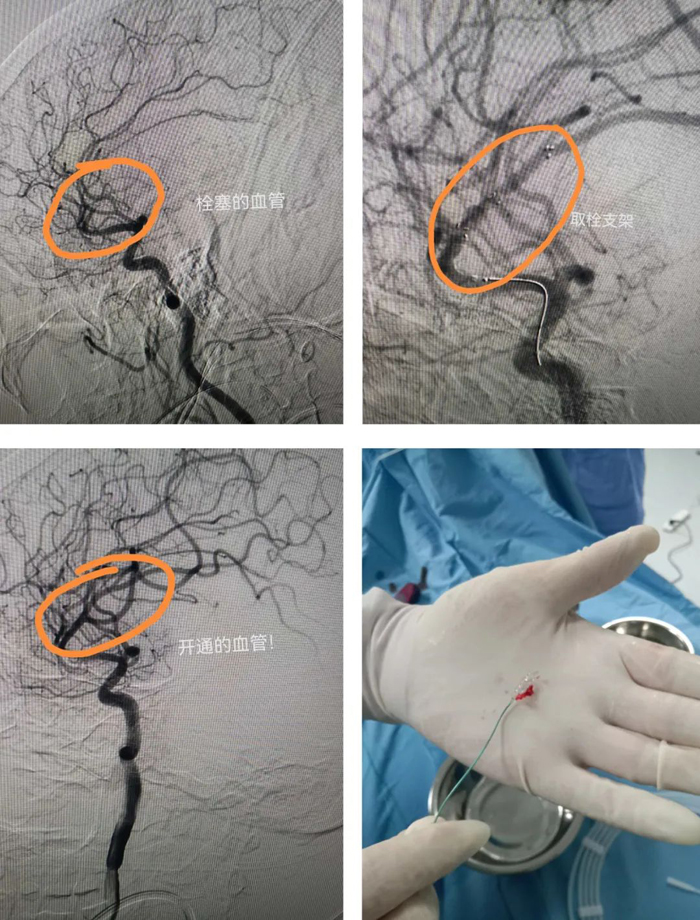

家屬簽字同意后,立刻將患者轉(zhuǎn)運(yùn)到介入室。造影提示患者為右側(cè)大腦中上干閉塞,大腦中動(dòng)脈m2段閉塞,取栓困難,風(fēng)險(xiǎn)很大。馬主任知難而上,快速上微導(dǎo)管和取栓支架,一次取栓成功,患者大腦中動(dòng)脈上干恢復(fù)血流。術(shù)后,患者肢體活動(dòng)完全恢復(fù)正常。整個(gè)過程僅用50分鐘!

腦梗死致死率、致殘率高,目前最好的治療是溶栓,但該患者正服用抗凝藥物,是溶栓禁忌癥。因此,動(dòng)脈取栓治療是該患者的最佳治療方法,可最大限度減少后遺癥的發(fā)生。(宋正峰)